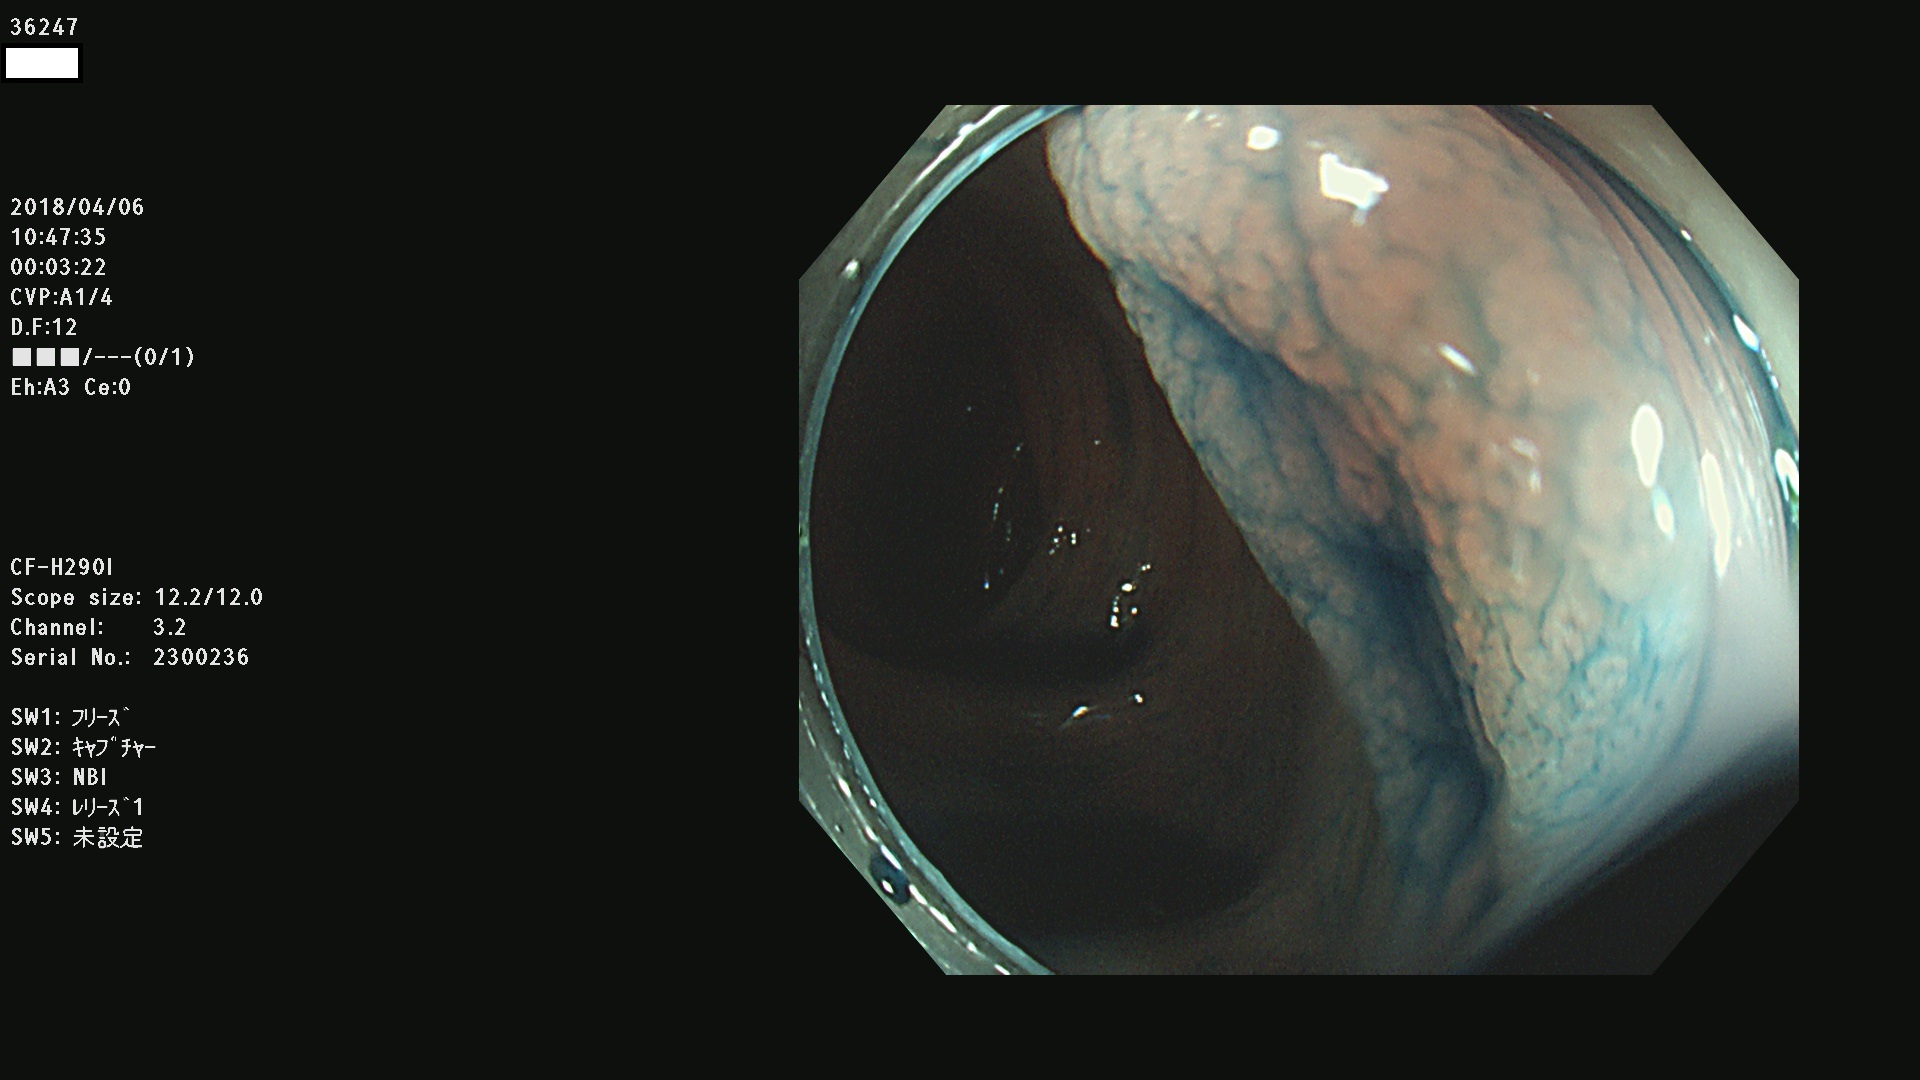

36201 36202 36203 36205 36207 36209 36210 36212 36213 36214 36215 36217 36220 36221 36222 36224 36225 36226 36227 36229 36230 36231 36232 36235 36236 36238 36240 36243 36244 36246 36247(SSAPのみ。SPS) 36248 36249 36251 36252 36253 36254 36255 36256 36257 36258 36259 36261 36262 36264 36265 36267 36269 36270 36272 36274 36275 36276 36279 36280 36281 36283 36285 36288 36289 36291 36292 36295 36296 36297 36299

発見困難で危険性の高い平坦型病変(上記100名より抽出)